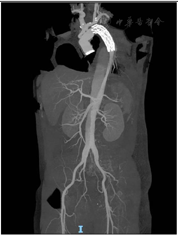

CTA示:主动脉夹层术后,主动脉根部见金属瓣环影,主动脉弓降部及胸主动脉可见高密度金属支架影,主动脉弓上方见小片高密度影。主动脉弓及降主动脉起始部形态欠规整。胸降主动脉于气管分叉出水平至肝顶水平管腔明显扩张,直径约52 mm,区域内见数个溃疡形成,管壁增厚。腹主动脉于肾下极水平至度主动脉分叉处管腔扩张,直径约35 mm。主动脉全程见局限性极弥漫性混合斑块及钙化斑块,管腔不均匀轻度狭窄(影像学结果详见图1)。

患者继发胸腹主动脉瘤后二次入院,入院时遵医嘱给予持续心电监护及氧气吸入,术前予以止痛、降压、控制心率等对症处理,完善术前检查,择期行"胸腹主动脉瘤切除人工血管置换+肋间动脉重建+腹主动脉-双股动脉Y型人工血管转流术"。术后常规进行抗感染、对症处理、稳定内环境等治疗,并给予综合护理干预:包括循环系统、神经系统、呼吸系统、泌尿系统、消化系统护理及皮肤、康复、心理护理等综合护理。经积极治疗后,患者下肢肌力恢复至4级,康复出院(患者行该手术前、后的CTA结果对比详见图2)。